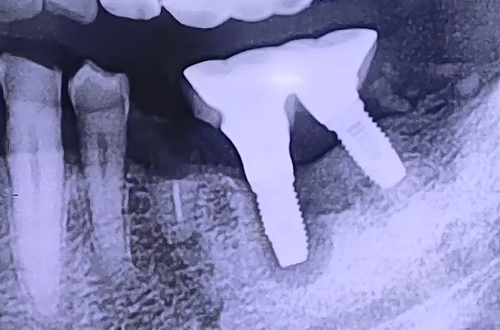

AFTER

이렇게 비뚤게 식립된 임플란트는 환자분들께서 열심히 관리를 해 주어도 그 사이에 생긴 틈새 등의 이유로 원활하게 관리가 이루어지기 어려워 주위염을 불러올 수 있죠. 따라서 기존 임플란트와 그 앞에 남아있는 치아 뿌리를 제거하고 재수술을 진행하였습니다.

재수술 후 환자분께서는 같은 쪽 윗니 임플란트에서 또 통증이 느껴진다고 하시어,윗니도 뒤이어 치료해 드릴 예정으로 추가 수술 진행하게 되면 또 진료일지로 찾아뵙겠습니다. ^^